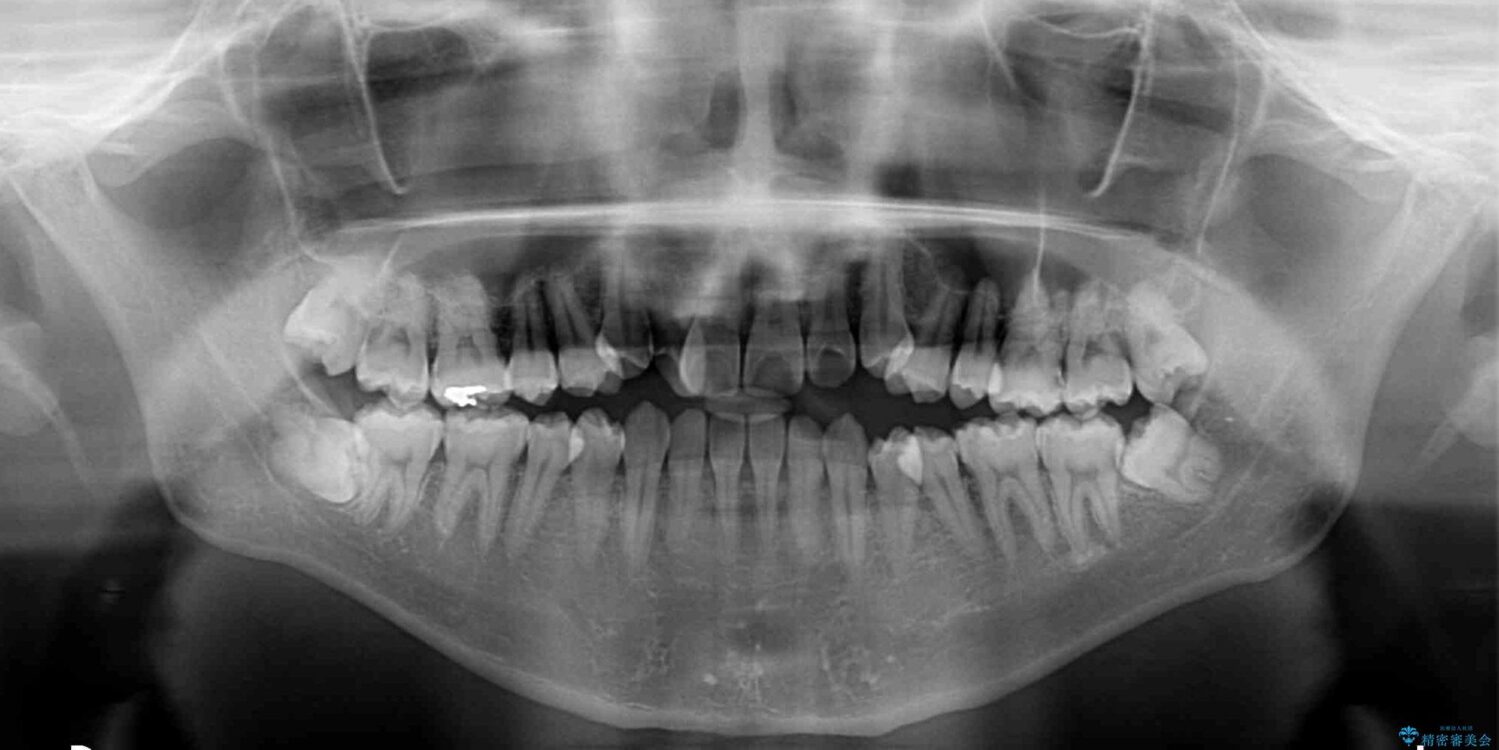

治療前

• 左右の八重歯が気になる ワイヤー装置での咬み合わせ改善 治療前画像